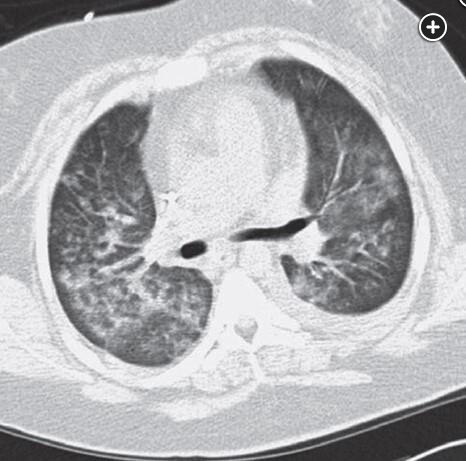

DAH CT finding includes consolidation or ground glass opacities related: DAH diffuse alveolar hemorrhage tags: #literature #pulmonology ground glass: consolidations: 1 Links to this note DAH diffuse alveolar hemorrhage DAH CT finding includes consolidation or ground glass opacities Footnotes SEEK Questionnaires ↩